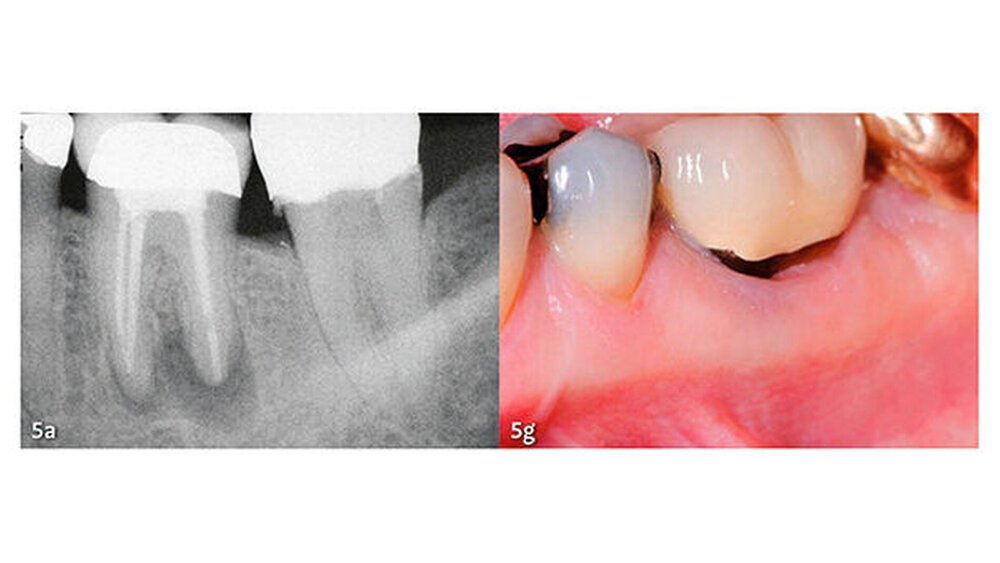

Klinische Studien

Die wesentlichen Daten von klinischen Studien über die Anwendung von MTA als retrogradem Füllmaterial sind in Tabelle III zusammengefasst. Die erste klinische Studie mit Auswertung der Erfolgsrate nach MTA-Anwendung in der apikalen Chirurgie wurde von Chong et al. (2003) publiziert - es war auch gleich die erste randomisierte Studie, welche MTA mit einem anderen retrograden Verschlusszement untersucht hat. Generell zeigen alle klinischen Studien sehr hohe Erfolgsraten für MTA in der apikalen Chirurgie (83,7% bis 96%). Die von uns 2014 publizierten Langzeitdaten (5 Jahre Beobachtungsdauer für alle behandelten Zähne) mit einer Erfolgsrate von 92,5% deuten auf eine sehr gute Stabilität und auf ein hohes Abdichtungsvermögen von MTA (von Arx et al. 2014) (Abb. 4 und 5).

Die Dokumentation der 10-Jahresdaten ist im Gange, und die bisherige Analyse deutet auf eine konstant hohe Erfolgsrate auch nach zehn Jahren (Abb. 6). Eine systematische Auswertung mit Meta-Analyse aller bis 2007 publizierten retrograden Füllmaterialien in Vergleichsstudien mit mindestens zwei getesteten Verschlussmaterialien ergab für MTA die höchste Wahrscheinlichkeit einer periapikalen Ausheilung (91,4%) (von Arx et al. 2010a).